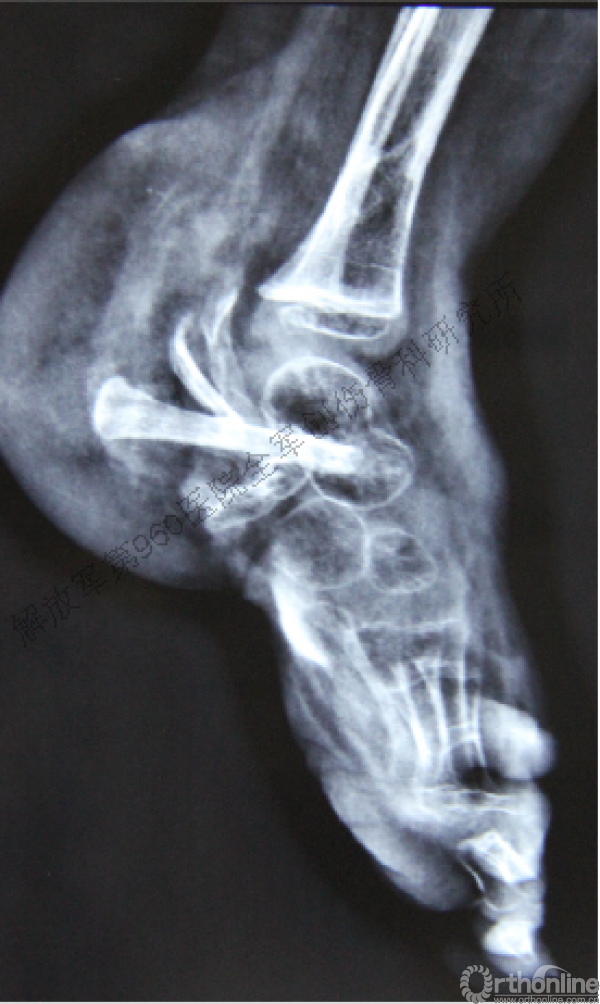

术后6周X线